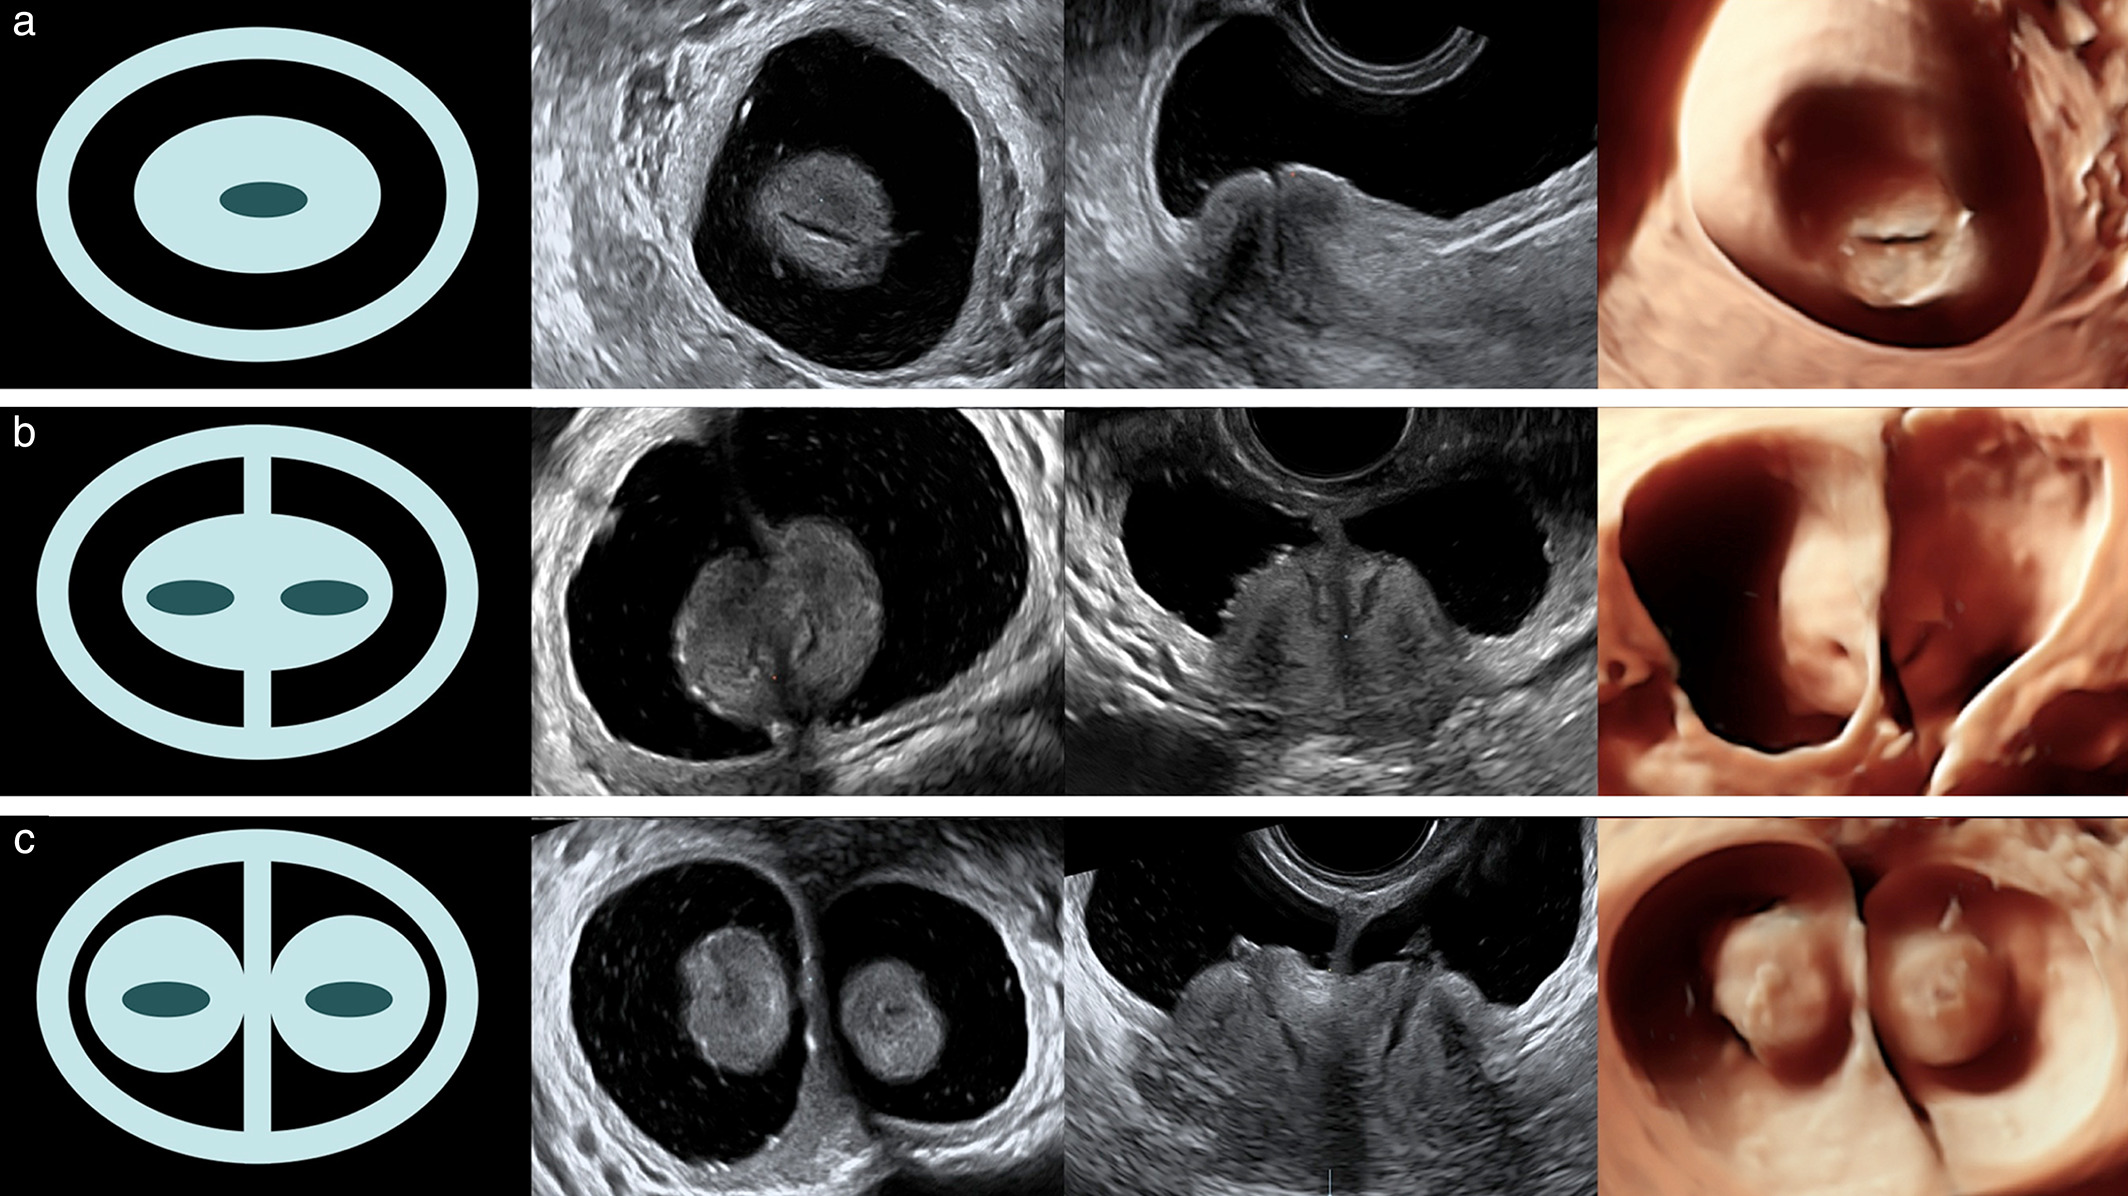

Longitudinal vaginal septum: a proposed classification and surgical management

Two- and Three-Dimensional Ultrasonography and Sonohysterography versus Hysteroscopy With Laparoscopy in the Differential Diagnosis of Septate, Bicornuate, and Arcuate Uteri

Congenital Uterine Malformation by Experts (CUME): better criteria for distinguishing between normal/arcuate and septate uterus?